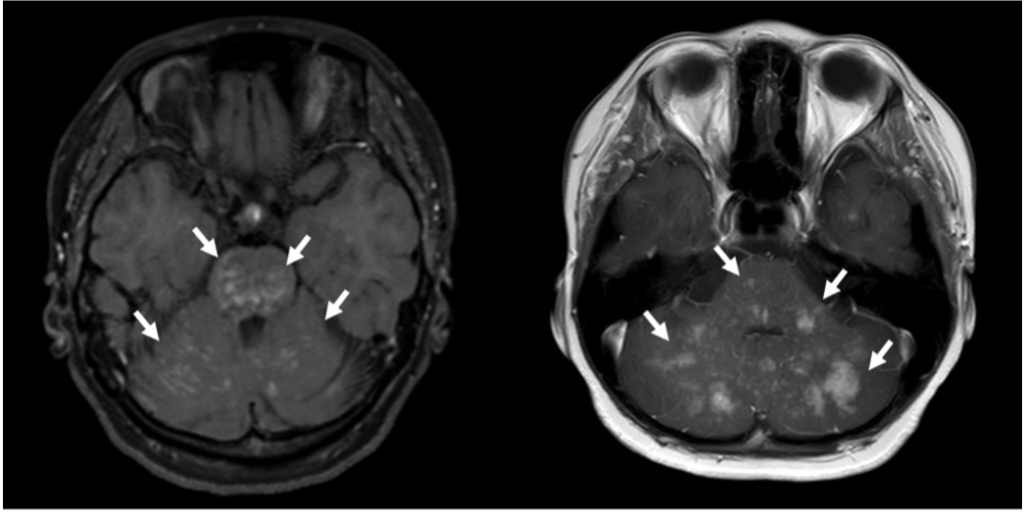

CLIPPERSは、脳幹や小脳を中心に、脳や脊髄といった中枢神経に炎症が生じる疾患です。MRI検査で小さな病変が多数認められ、ステロイド治療が有効であることが特徴とされています。一方で、炎症が起こる原因は十分に解明されておらず、診断や治療方針の判断が難しい場合もあります。

研究グループは、CLIPPERS様のMRI画像所見および臨床像を呈し、再燃を繰り返していた10~20代の2症例について詳細な解析を行いました。遺伝子解析によりUNC13D遺伝子の異常を同定し、さらに免疫細胞の機能を評価する検査でも異常が確認されたことから、2症例はいずれもFHL3と診断されました。FHL3に対する根治治療として同種造血幹細胞移植が位置づけられていることを踏まえ、2症例に移植治療を実施した結果、症状の改善が認められました。

- CLIPPERS:Chronic lymphocytic inflammation with pontine perivascular enhancement responsive to steroidsの略。脳幹(特に橋)や小脳を中心に脳や脊髄に炎症が起き、造影MRIで小さな点状の造影所見が多数みられることが特徴。多くの例でステロイド治療に反応するが、なぜ炎症が起きるのかは十分に分かっていない。 ↩︎